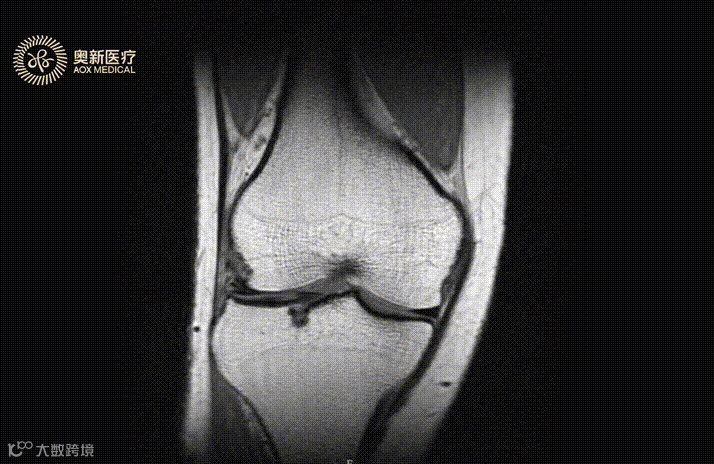

骨关节炎

不少人在上下楼梯、久坐、弯腰时,膝、肩、腰等部位作痛,按摩、热敷……用了很多办法仍无法根除或缓解疼痛,反而随着年纪增长更加严重,甚至影响正常身体活动。这很可能是患上了一种常见且会致残的疾病,骨关节炎。

世界卫生组织已经把膝关节和骨关节炎列为和心脑血管疾病具有同样危害的健康杀手之一。